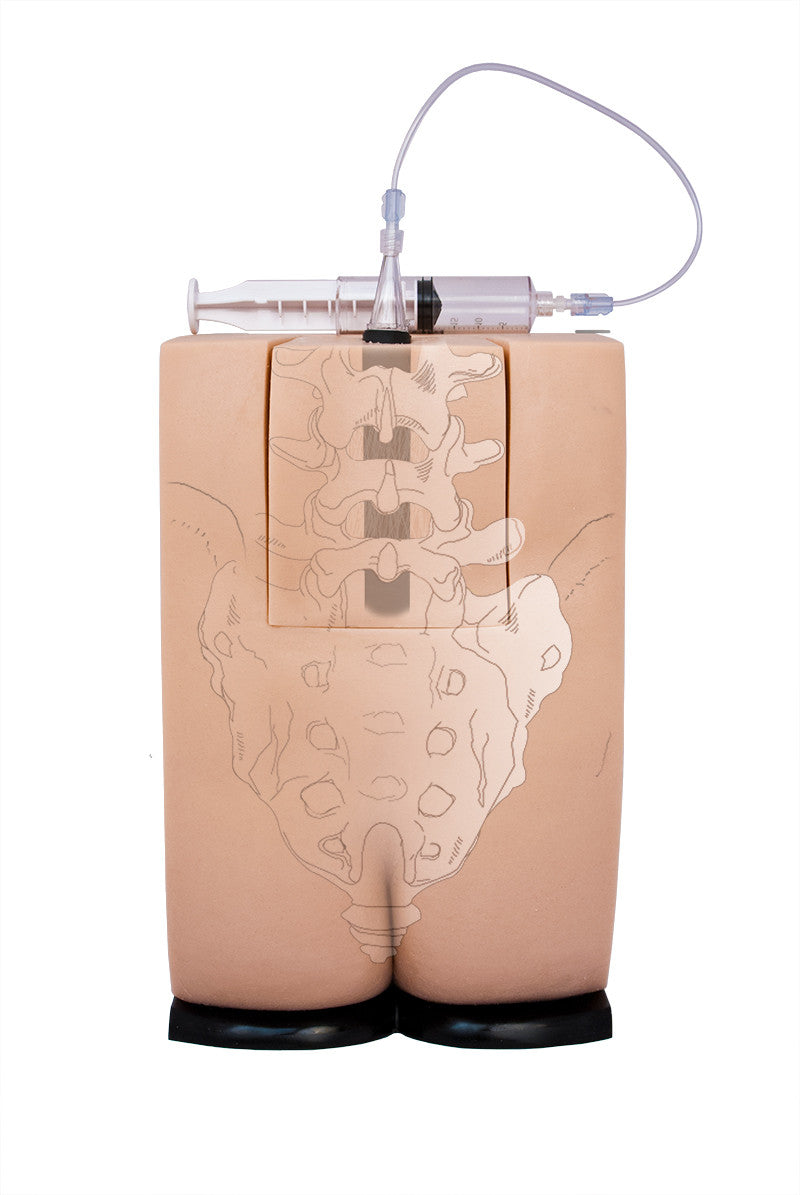

Train students and healthcare professionals in essential epidural injection skills using our highly realistic spine simulators, designed to enhance clinical training and procedural accuracy.

Geriatric LOR Insert (2) for Epidural and Spinal Injection Trainer

Geriatric LOR Insert for Epidural and Spinal Injection Trainer

Replacement Skin for Epidural and Spinal Injection Trainer

Standard LOR Kit (2) for Epidural and Spinal Injection Trainer

Our range of epidural injection trainers includes detailed anatomical models that replicate the lumbar and thoracic spine, providing a hands-on learning experience for anaesthetists, medical students, and pain management specialists. These advanced simulators allow users to practise needle placement, identify key anatomical landmarks, and develop proficiency in administering epidural and spinal anaesthesia with confidence. Ideal for medical schools, hospitals, and professional training programmes, these epidural trainers support skill development in regional anaesthesia, labour pain management, and spinal procedures. With lifelike materials that simulate real patient responses, our models offer a realistic and immersive training experience.